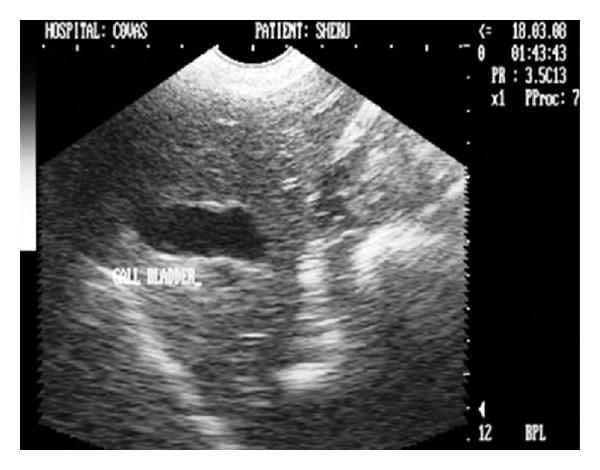

Hepatic disease is often treatable and has a predictable prognosis when a definitive diagnosis is made. The aim of clinicopathological evaluation of hepatobiliary affections is to identify and characterize hepatic damage and dysfunction, identify possible primary causes of secondary liver disease, differentiate causes of icterus, evaluate potential anaesthetic risks, assess prognosis and response to xenobiotics, and monitor response to therapy. This paper describes the different diagnostic methods and imaging techniques employed in diagnosis of hepatobiliary affections in dogs. Besides reviewing the significant clinical manifestations and imaging structural abnormalities in diagnostic approach to different hepatic affections, it also depicts radiographic, ultrasonographic, and wherever applicable, the laparoscopic characterization of different hepatic affections and target lesions encountered in clinical cases presented in the Teaching Veterinary Clinical Complex, COVAS, Palampur in the year 2007-2008.

肝病通常是可治疗的,一旦做出明确诊断,其预后是可预测的。肝胆疾病临床病理评估的目的是识别和描述肝损伤及功能障碍,确定继发性肝病可能的主要病因,鉴别黄疸的病因,评估潜在的麻醉风险,评估预后及对外源化学物质的反应,并监测治疗反应。本文描述了用于诊断犬肝胆疾病的不同诊断方法和成像技术。除了回顾不同肝病诊断方法中的重要临床表现和成像结构异常外,还描述了2007 - 2008年在帕兰普尔兽医临床综合教学中心(COVAS)出现的临床病例中不同肝病及目标病变的放射学、超声学特征,以及在适用情况下的腹腔镜特征。